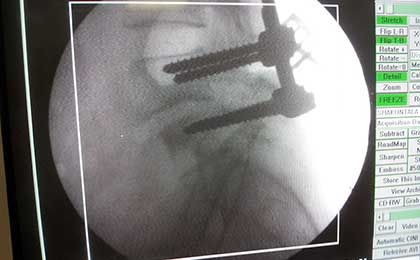

INTRA OP SPINE FIXATION

traumatic spine fix intraop